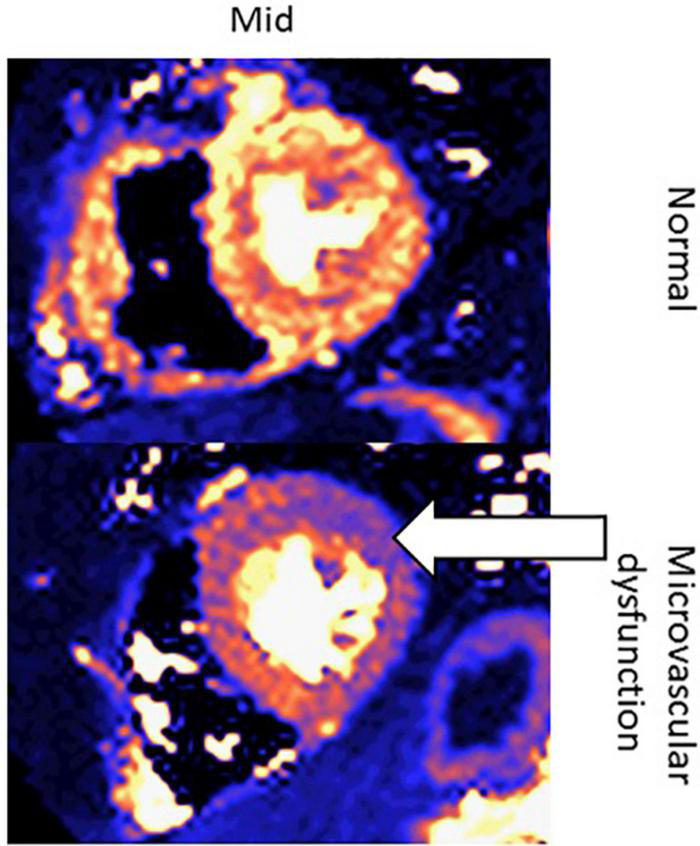

Another new application of CMR in oncology patients may be to evaluate microcirculatory damage, as one of the effects of cardiotoxic chemotherapy is microcirculatory damage to the myocardium (74). Studies have shown that cardiotoxic chemotherapies lead to a decrease in nitric oxide-mediated dilation in endothelial cells, which is associated with increased risk of various cardiovascular risk factors, such as heart failure and hypertension (75). One study assessing the direct effect of doxorubicin on human coronary microvascular function ex vivo found that among adult human coronary microvessels treated with doxorubicin, flow-mediated dilation (FMD) and coronary arteriolar function were significantly impaired (76). Moreover, CMR has been used to assess microcirculatory damage, as seen in Figure 13 (76–79).

FIGURE 13

Quantitative perfusion CMR assessment of myocardial microcirculatory damage in a normal patient vs. cancer patient undergoing cardiotoxic chemotherapy. These are two left ventricular short-axis images of the mid-segment myocardium. The top row contains an image from a healthy patient, whereas the bottom row contains an image from a patient with microvascular dysfunction due to chemotherapy. The white arrow indicates the area of the left ventricle with the greatest microvascular dysfunction.